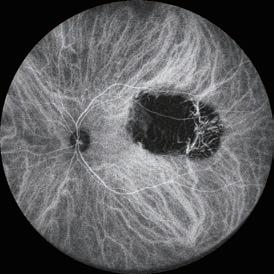

In addition to MMP-9, levels of other pro-inflammatory markers increased progressively across the three “control groups”, were significantly greater in the subclinical inflammation I and II groups compared to controls with no inflammation, and were almost identical in the subclinical inflammation II and DED cohorts.

The testing, sample preparation, and platform processing take 90 minutes. In addition to MMP-9, the test measures levels of four pro-inflammatory cytokines (interleukin [IL]-1β, IL-6, IL-17A, TNF-α), VEGF, soluble ICAM-1, and IL-10, an antiinflammatory cytokine included to help understand the balance between pro- and anti-inflammatory factors, Dr Shirodkar said.

None of the study groups had elevated levels of IL-10 or VEGF, Dr Shirodkar reported.

The system uses a customised ELISA platform (Bio-M Pathfinder) to measure eight soluble factors in tear fluid extracted from Schirmer’s strips. The developers conducted a study that included 107 patients with DED diagnosed per TFOS DEWS II guidelines, 125 patients with keratoconus, and 389 controls scheduled for refractive surgery who had no overt signs of DED. The controls were further stratified into three groups based on matrix metalloproteinase-9 (MMP-9) level: no inflammation <50,000 pg/mL (n=214); subclinical inflammation I 50,000 to 162,000 pg/mL (n=95); and subclinical inflammation II >162,000 pg/mL (n=80).

Currently, the researchers are generating additional data sets to improve the robustness of the analysis and are adding to the keratoconus cohort to hopefully identify grade-specific differences and progression-related changes.

“We hope to popularise our concept of targeted therapy for DED that uses a biomarker-based algorithm to rationalise the manner in which we deliver care to these patients,” Dr Shirodkar said.

EUROTIMES | SEPTEMBER 2022